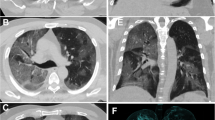

A typical finding of the early stage of COVID-19 pneumonia described on HRCT is the evidence of subsegmental vessel enlargement (> 3 mm diameter) within the areas of GG [33,34,35,36,37]. This sign is possibly related to hyperaemia and vessel wall injury induced by inflammation [34]. Indeed, lung damage caused by SARS-CoV-2 infection is linked to the development of a “cytokine storm”, which can cause lung endothelial cells injury and apoptosis [38], ultimately leading to diffuse endothelial damage and the development of vascular microthrombosis [17]. Described in more than 80% of cases in some cohorts [35, 37] and with a pooled prevalence of 72.9% according to Adams et al. [32], this sign may help to differentiate COVID-19 from other viral pneumonia [39] (Fig. 1). Later in the progressive phase, as consolidation replaces the areas of GG, this sign becomes barely visible due to the obscuration of the pulmonary vasculature, while during absorption vessel caliber returns normal. Therefore, vessel enlargement can be used not only to assess the diagnosis of COVID-19 pneumonia, but also as a marker of the early stage of disease.

a Patient with COVID-19 pneumonia. The CT scan shows a crazy-paving pattern with typical predominant subpleural and bilateral distribution at the lung bases; note the presence of "enlarging vessel" sign within the areas of increased lung density (arrows). b Patient with H1N1 influenza-associated pneumonia. The CT scan shows multifocal small areas of consolidation and perilobular opacities with bilateral subpleural distribution at the lung bases, associated with some GG areas in the left lower lobe; note the normal caliber of pulmonary vessels in the proximity of the pulmonary abnormalities (arrowheads)

Particularly, GG opacities increase in size, with a possible diffuse distribution of the lesions. Smooth interlobular septal thickening can appear within the GG areas, leading to a crazy paving pattern on HRCT [30], which has been reported in up to 34.9% of patients [32]. At the same time, GG opacities progressively turn into consolidation, thus determining the development of a mixed pattern with a combination of consolidative and GG areas [21, 24] (Fig. 2).

CT scans of a patient with COVID-19 pneumonia demonstrating the typical evolution of the disease by phases. a In the early phase, GG opacities are the predominant finding. b 10 days after the onset of symptoms (progressive to peak phase) more extensive GG areas with crazy paving appearance and typical distribution at the lung periphery are observed. c One week later, GG areas decline and lead to the appearance of multifocal consolidation with mild parenchymal distortion